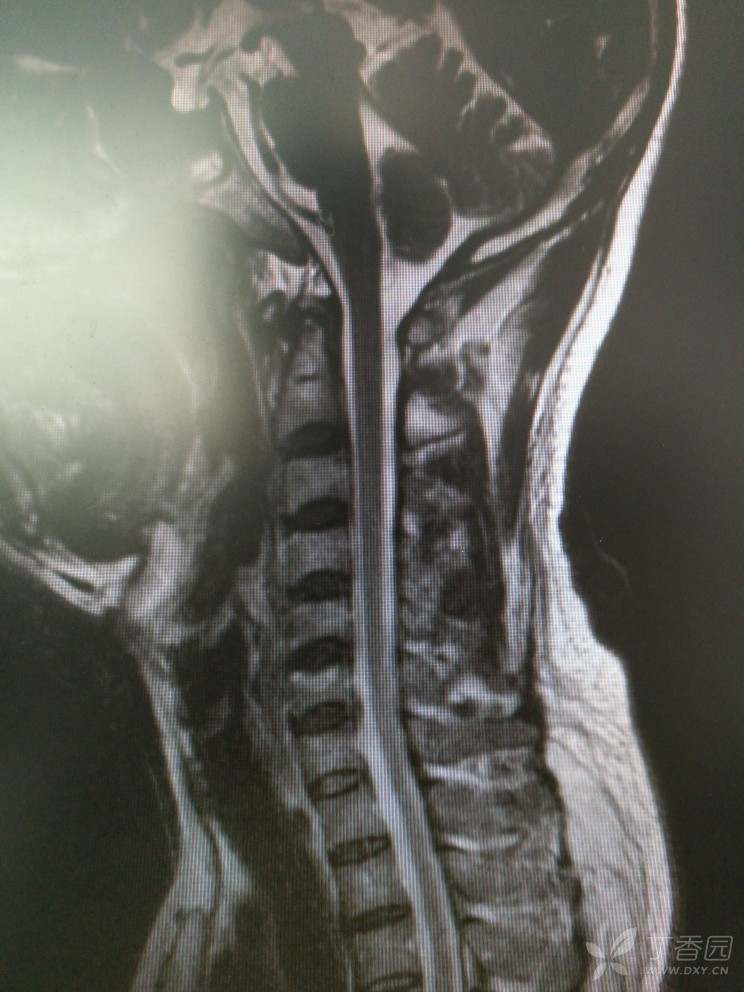

入院查MRI

我想问还是考虑L4/5 L5/S1椎间盘的变性引起的吗?